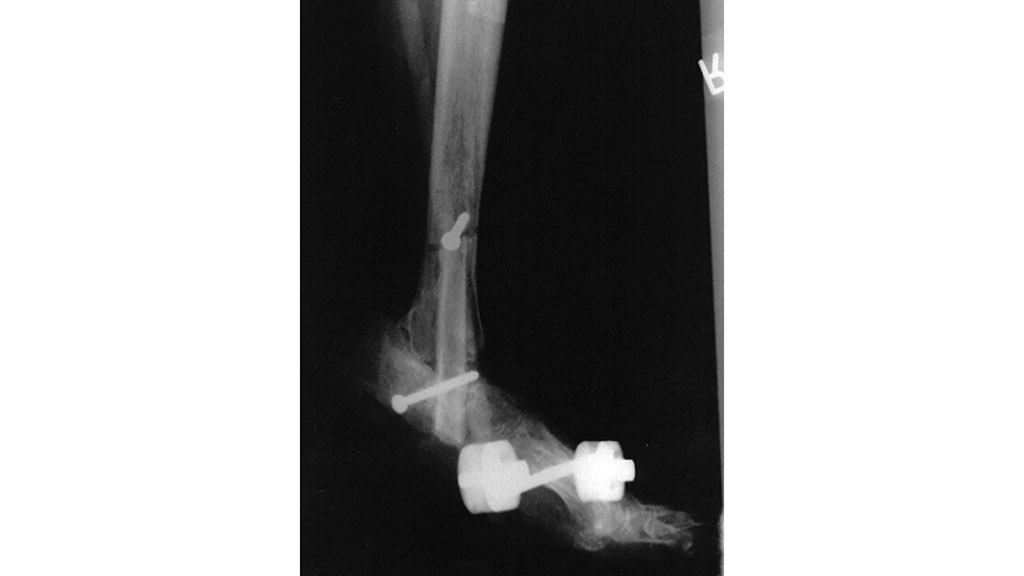

Eine Versorgung des Diabetischen Fußsyndroms erfolgt vorrangig durch die Gefäßchirurgie. Aber nur etwa 30 bis 40 % dieser Füße haben ein wirkliches therapeutisch anzugehendes Gefäßproblem (Angiopathie), welches durch verschiedene operative Maßnahmen wie das Ausschälverfahren (Desobliteration), die Bypasschirurgie (Vene oder Kunstprothese) und/oder die Kombination mit einem endovasculären Verfahren (z. B. Ballonerweiterung) korrigiert werden sollte (Abb. 1). Vorrangig sind beim Diabetes Veränderungen der Gefäße im Unterschenkel-Fußbereich charakteristisch, sodass insbesondere solche Verfahren eingesetzt werden sollten, die eine verbesserte Durchströmung in den kleinen Gefäßen erzielen (perkutane transluminale Angioplastie), ohne dabei einen zusätzlichen Weichteilschaden im Fuß-Unterschenkel zu erzeugen.

Bei drohenden Ulzerationen durch Knick‑, Klump- oder Sichelfuß sind auch innere Osteosynthesen durch Markraumnagel oder AO-Schrauben geeignet. Bei wiederholten Infekten nach Osteosynthesen infolge von Instabilität bzw. Infekten des Osteosynthesematerials ist alternativ auch eine biologische Arthrodese mittels autologem Fibulaspan möglich (Abb. 8).